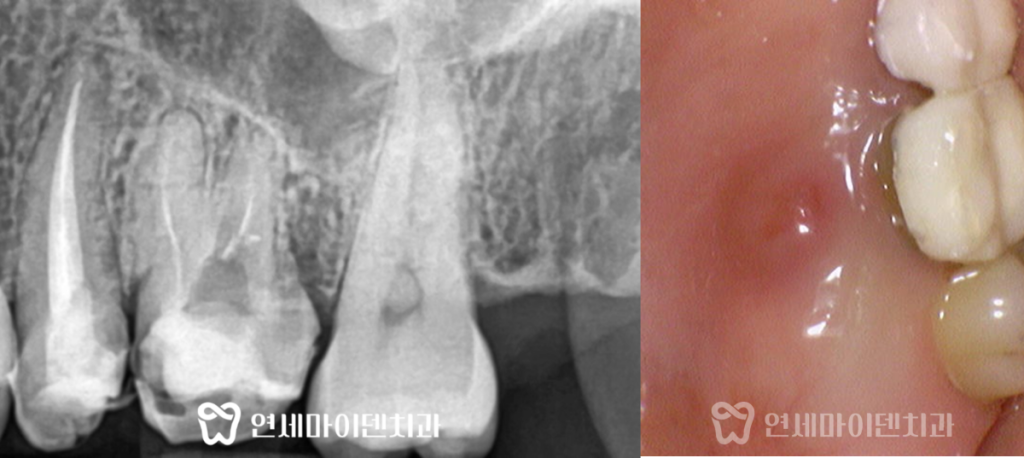

수술은 뼈 보존을 고려해 즉시 식립 후

안정적으로 골유착을 유도하였고,

수술 부위의 잇몸도 건강하게 치유되었습니다.

3D 네비게이션 임플란트를 통해

임플란트 식립 위치를 계산하여

정밀하게 치료 계획을 세워줍니다.

발치 후 염증 조직을 깨끗하게 제거하고

계산된 위치에 임플란트를 식립하는

발치 즉시 임플란트를 시행하였습니다.

임플란트 식립 한 달만에

식립 부위가 깨끗하게 아무는 것을 확인할 수 있습니다.

임플란트가 안정적으로 자리잡고

잇몸이 회복된 후에 2차 임플란트 수술을 진행합니다.